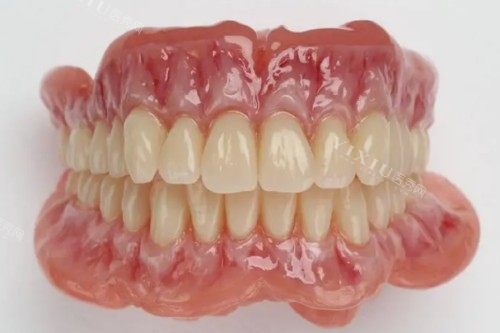

BPS义齿牙全称为“生物功能模拟义齿”,它融合了现代材料科学、生物力学和智能化技术,为缺失牙齿的患者提供了一种更加舒适、美观且功能强大的修复选择。本文将从多个方面深入解析BPS义齿牙的优势,帮助大家更好地了解这一口腔修复技术。

美观是义齿修复的重要考量因素之一,而BPS义齿牙在这方面表现出色。它采用了智能化技术,能够根据患者的牙齿形态、颜色和咬合关系进行精细设计和制作。BPS义齿牙的颜色与天然牙齿极为接近,无论是色泽、透明度还是光泽度,都能达到以假乱真的结果。此外,其形态设计也更加自然流畅,与患者的口腔结构理想契合,无论是微笑还是说话,都不会露出明显的假牙痕迹,极大地提升了患者的自信心和社交体验。

BPS义齿牙的制作过程充分体现了个性化定制的理念。每一位患者的情况都是独特的,因此BPS义齿牙的制作团队会根据患者的具体需求和口腔状况,量身定制适合的义齿方案。从牙齿的形状、大小、颜色到咬合关系的设计,每一个细节都经过精心调整和优化,以确保义齿能够理想地融入患者的口腔环境,满足患者对美观和功能的双重需求。